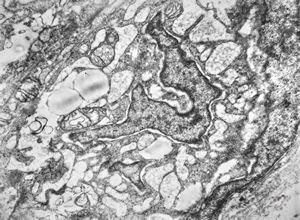

M,15y. | neurinoma - orbita